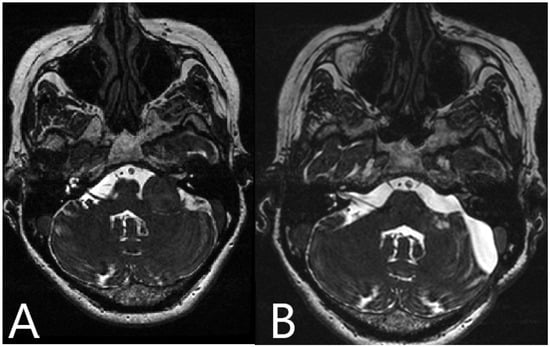

Illustrative Cases